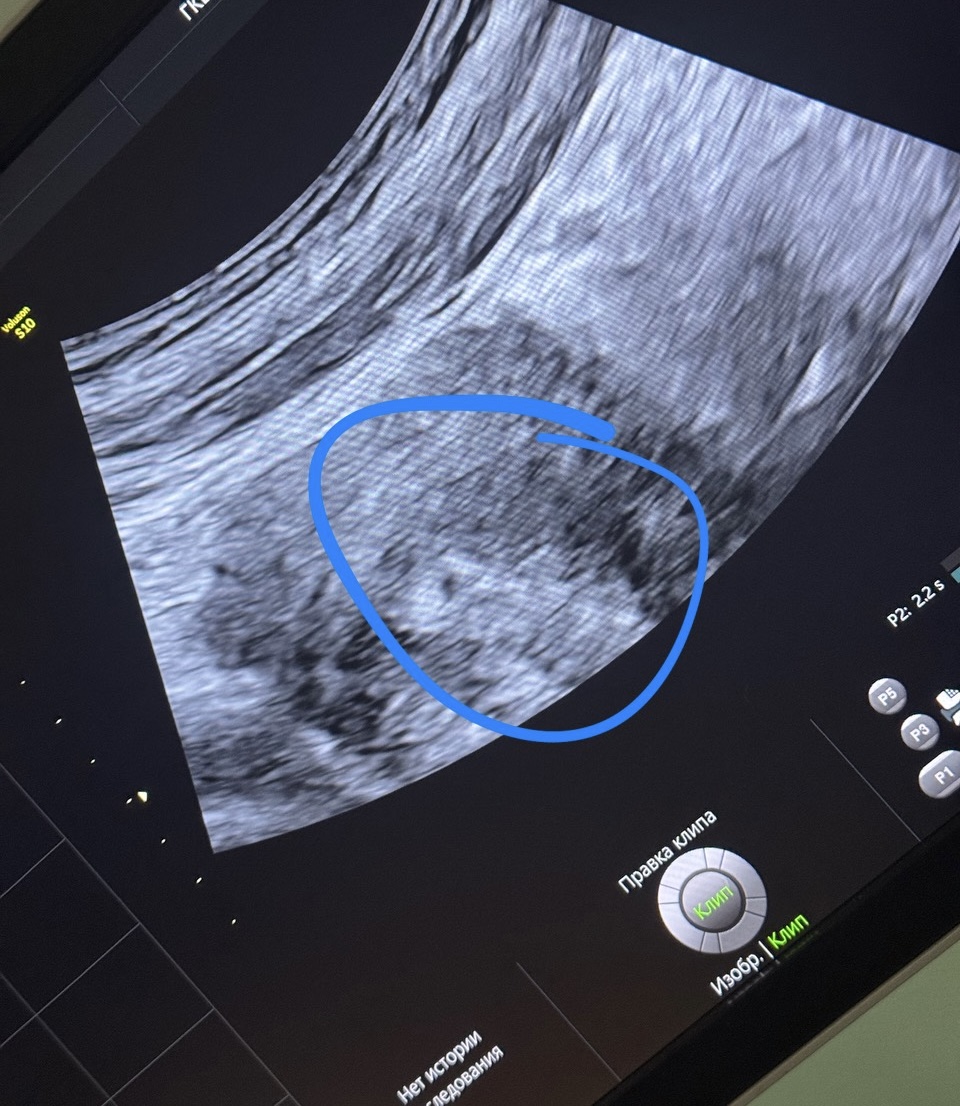

пока все еще лежу в больнице, отхожу после операции. трубки все из меня вытащили слава богу, стало легче. эндометрий немного отслаивается, но после свечей и дюфастона вроде стало получше. просто надеюсь что удастся сохранить беременность после такого и малыш будет здоровым. хгч растет, сегодня 360, позавчера был 129. ПЯ в матке 2 мм. малыш цепляется за эту жизнь как только может 😅 я на прогестероне.

*лопнул оказывается не яичник а желтое тело.